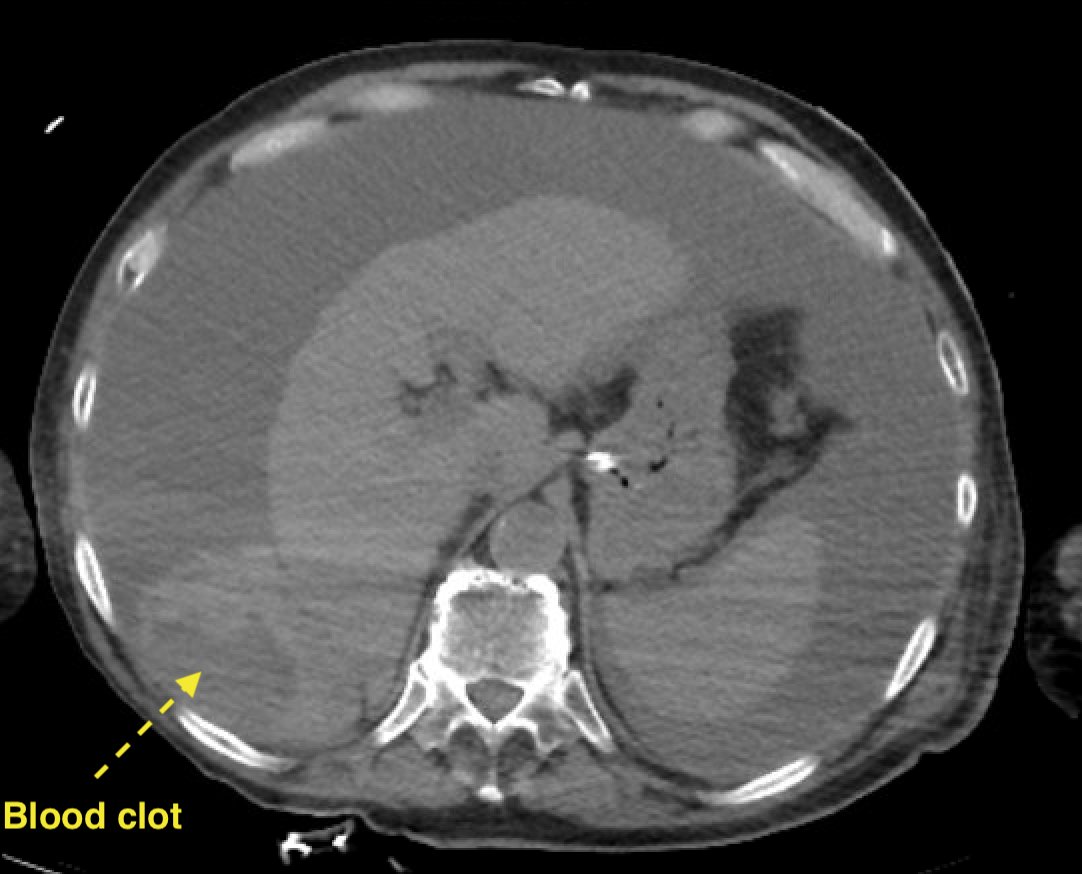

ICU stories: Elderly pt w PMHx of CAD/COPD/CKD/DM2/cirrhosis c/b esoph varices + ascites requiring p...

ICU stories: Elderly pt w PMHx of CAD/COPD/CKD/DM2/cirrhosis c/b esoph varices + ascites requiring paracentesis (most recent a week earlier)/anemia of chronic dz/”etc” presented to...